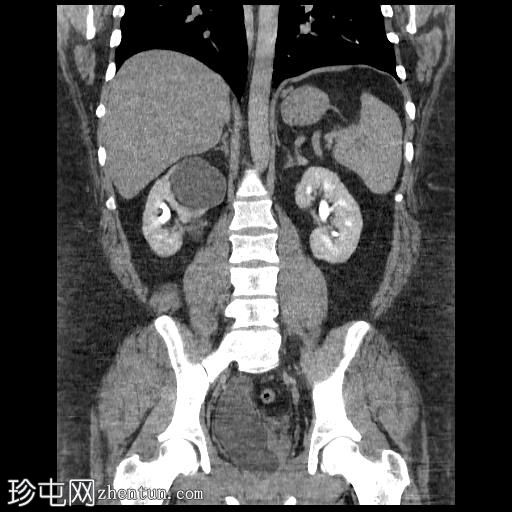

冠状位(口服造影剂)

右肾集合系统完全重复。上肾集合系统的输尿管异位开口于前列腺尿道,导致上游集合系统显著扩张。这引起肾实质的慢性改变,包括上肾组织变薄和上肾盏排尿功能障碍。

相反,右肾下肾集合系统的输尿管位置正常,无扩张或结石迹象。

左肾和输尿管外观正常。

右肾重复畸形伴异位输尿管的CT表现。异位输尿管是一种先天性异常,指输尿管在异常位置开口于膀胱。

男性异位输尿管可连接至膀胱下段、尿道后段、精囊、输精管、射精管,或极少数情况下连接至直肠。